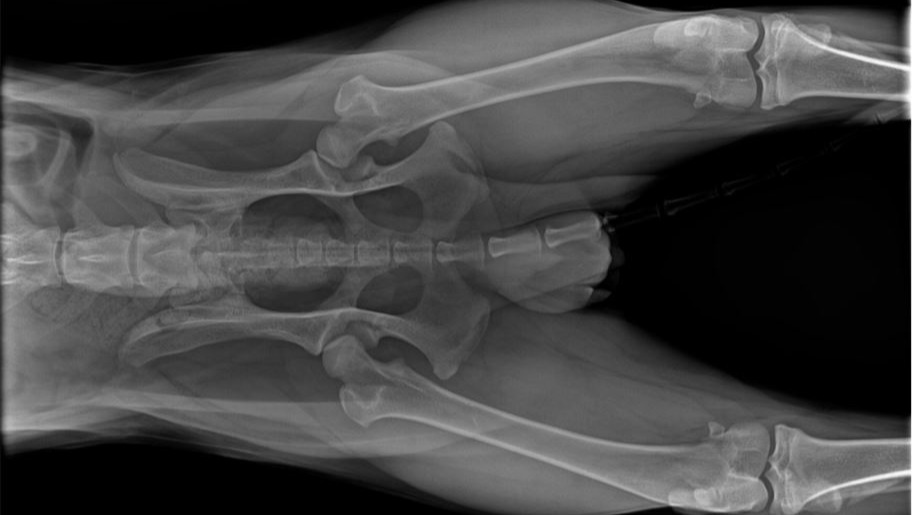

We took him to local vets, who recommended specialists, who diagnosed Dave with advanced congenital hip dysplasia. The only reasonable solution is a double hip replacement, without which his condition will continue to deteriorate until pain and arthritis leave him unable to walk.